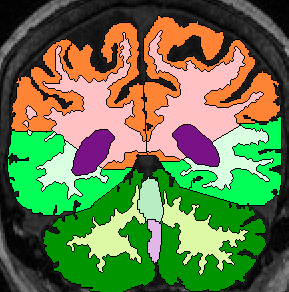

| Temporal Lobe White Matter: Anteriorly, simply relabel the cerebral white matter in the temporal lobe as temporal lobe white matter (fig 2). When the white matter becomes continuous from the temporal lobe to the frontal, draw a horizontal line laterally from the inferior Insula, then extract the temporal white matter, leaving it unlabeled for the time being (fig 3- this image show it labeled, however). Once the frontal lobe gray matter superior to the amygdala is gone, draw a straight horizontal line from one fronto-temporal junction (lateral sulcus) to the other and extract the temporal white matter (fig 4).

When parietal lobe shows up ventrally, draw a line from the medial parietal-temporal junction to the the lateral one(fig 5).

When occipital shows up inferiorly, extend the temporal boundry lines straight out until they intersect (fig 6). Finally, label all unlabeled extractions as Temporal White Matter. |